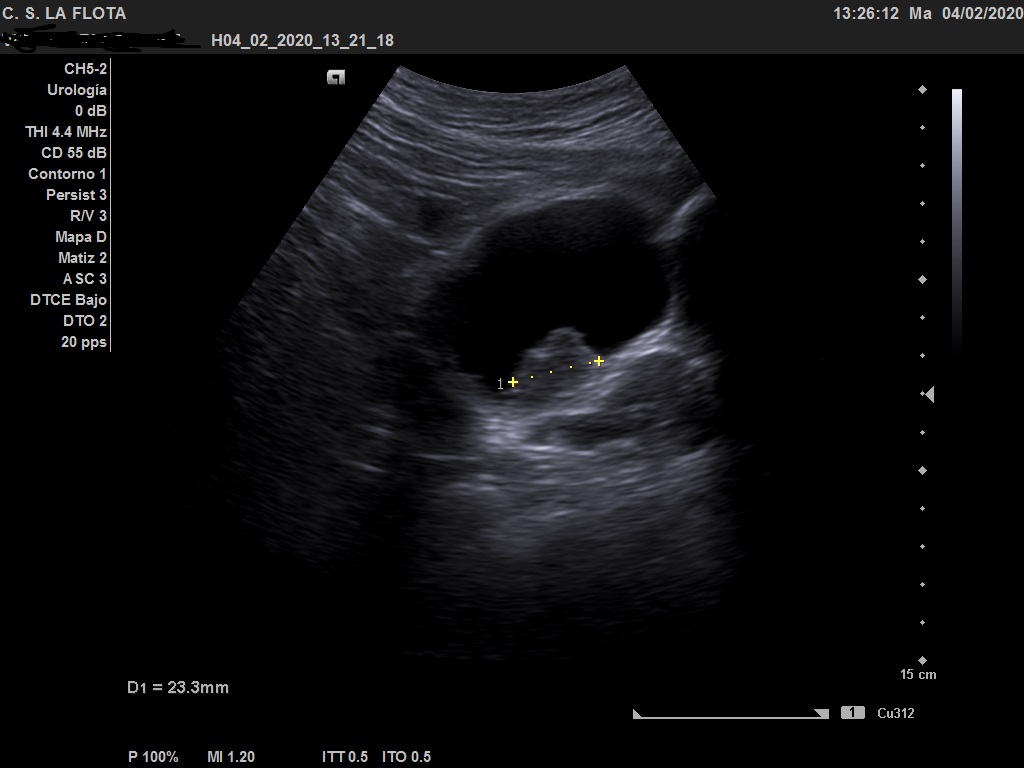

Ecografía clínica: riñones de tamaño y morfología normal, con buena diferenciación corticomedular y sin dilatacion de vias. En vejiga lesión polipoidea  de 25*18 mml.